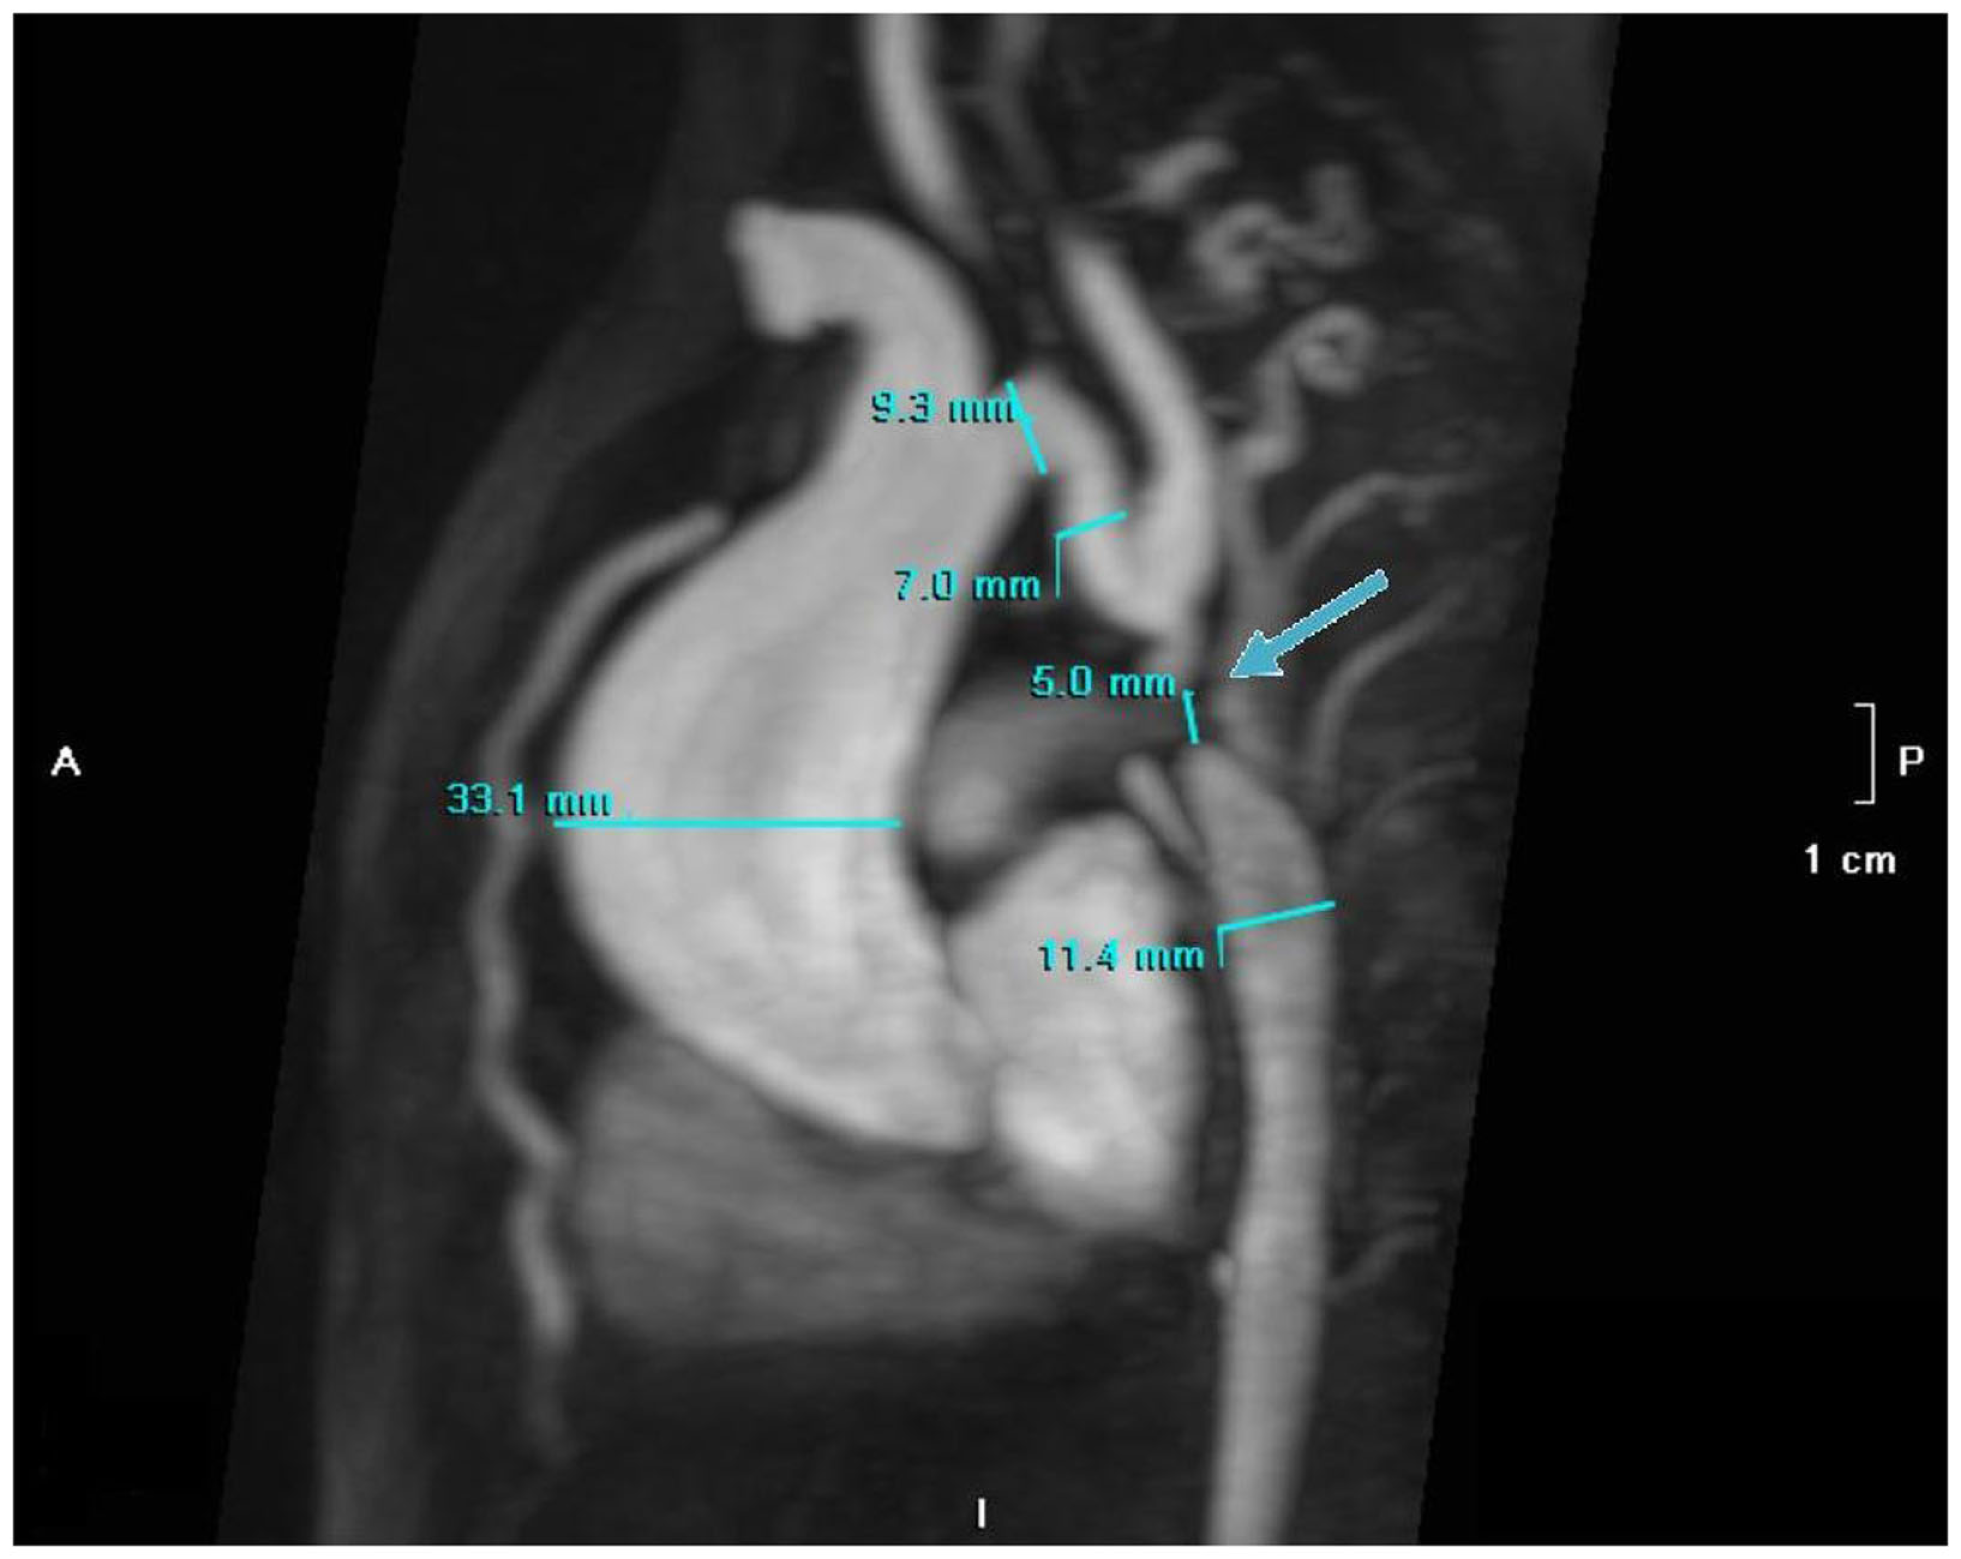

The electrocardiogram showed sinus rhythm with signs of left auricular hypertrophy, but no ventricular hypertrophy. The chest radiography (Figure 1) showed mild cardiomegaly (ICT 0.64) and an absent aortic knob, compatible with the diagnosis of coarctation. The echocardiography showed a bicuspid aortic valve (Figure 2) with severe stenosis (peak systolic gradient of 60 mmHg and mean of 30 mmHg), left ventricular hypertrophy (Z-score +3.3), preserved systolic and diastolic function (mitral E/A ratio 1.6; mitral A deceleration time 0.10 s, E/E′ 22 secondary to increased left heart filling pressure), and tortuous aortic arch with narrowing and acceleration of flow at the aortic isthmus (Figure 3). CMR with angiography showed absence of continuity between the ascending aorta distal to the left subclavian artery (Type 1) and the descending aorta, extending over 5 mm. There was a bend in the arch and diverticulum on either side of the zone of discontinuity, making the diagnosis of atresia rather than interruption of the aortic arch. There was no patent ductus arteriosus (PDA), no associated endofibroelastosis and the descending aorta was fed exclusively by massive systemic collateral circulation (Figures 4–6).

Figure 5

MR angiography with MIP reconstruction of the atretic aortic arch (5 mm) indicated by the arrow with dilatation (33 mm) of the ascending aorta, secondary to bicuspid aortic valve.